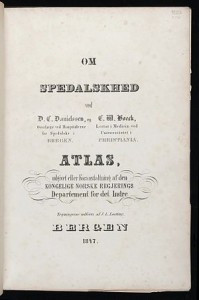

Hebra and Kaposi cite Danielssen and Boëck as having supplied the first clear description of the pathology of the disease. They then state emphatically that this much is now known: “that wherever lepra exists, at the present time, it always presents the same characters, and that the lepra of all countries is identical” (131). In addition, they determine that differences in symptoms in various localities are not significant and do not represent different varieties of the disease. Therefore, “in consequence of this discovery, all the names hitherto applied to the disease which are derived from its geographical position … must be given up, and one designation, founded on the history of the disease, and which may be understood by the physicians of all countries, must be substituted for them, once for all.” (131) They pronounce Lepra to be the name which they will use in future.

You Tube: On Leprosy (based on Danielssen and Boëck’s Atlas)

D C Danielssen and C M Boeck, Traite de la Spedalskhed ou Elephantiasis de Grecs (Bergen: D Bayer, 1847).